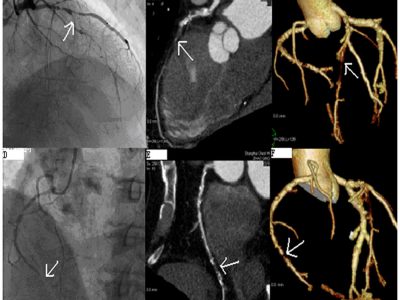

Cath PCI

PCI in ASCs & APP-led Cardiovascular Care

Are Ambulatory Surgery Centers equipped and ready for PCI? Our Quality Matters News ...